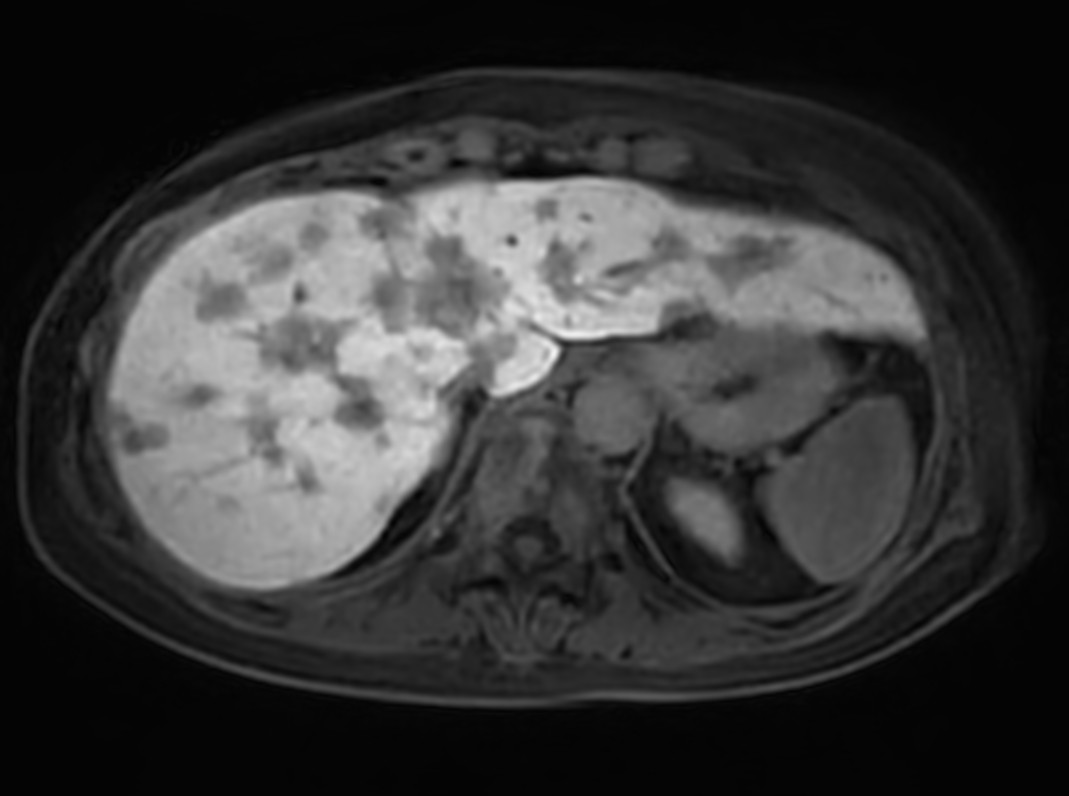

Liver metastasis with SmartSpeed Precise

Axial T2w SSh